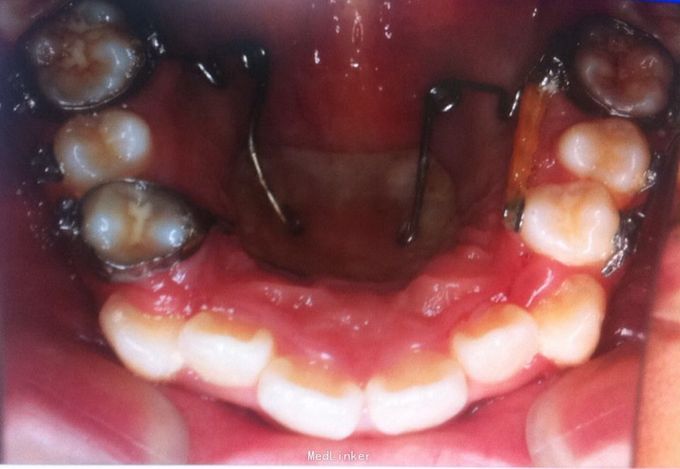

恒牙期 口内见摆式矫治器 左侧磨牙近中关系,右侧中性关系 前牙覆合覆盖正常 中线不正 上下牙列拥挤 张口度正常 关节有弹响 开口型异常